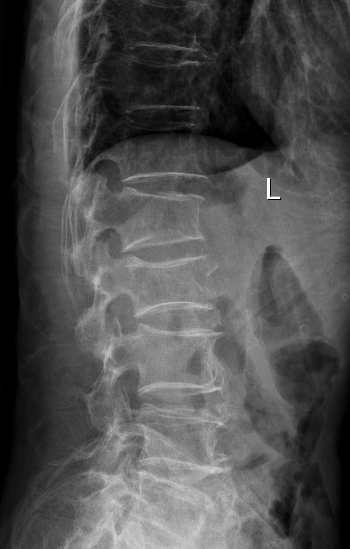

术后

术后

术前

术前